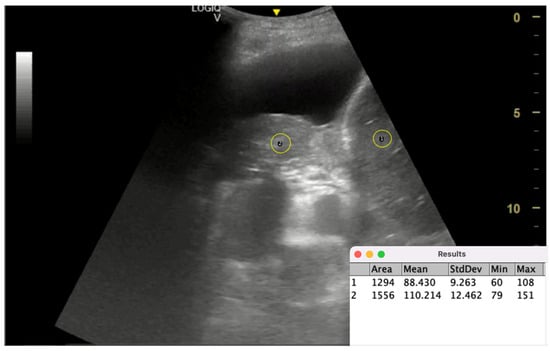

| lung/liver echogenicity (LLE) ratio | Compares grayscale pixel density of lung and liver via ImageJ software | Predicting lung re-expansion after pleural drainage | LLE > 1.6 predicts NEL with AUC = 0.77 | Simple, reproducible, quantitative | Limited validation, small study population, dependent on image quality | Lacks direct validation against; potential role as adjunct to manometry | Requires software (ImageJ) and proper grayscale calibration, moderately operator-dependent | Larger, multicenter studies, AI-based echogenicity analysis, validation in different effusion types |